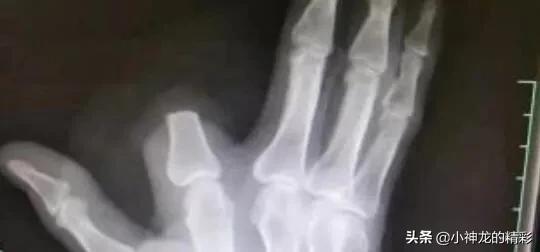

五步蛇还有一个特点,并不是形容他的毒素强烈,而是形容被咬之后的痛处。五步蛇的毒素是以蛋白质构成的溶血毒素,而这种毒素更是强烈出血性的,会导致极强的痛感。被咬中的人会出现伤口疼痛及出血现象。继而会肿大、起泡、组织坏死以及溃疡等,随后更会感到晕眩及心跳加速。伤口非常疼痛,难以忍受。